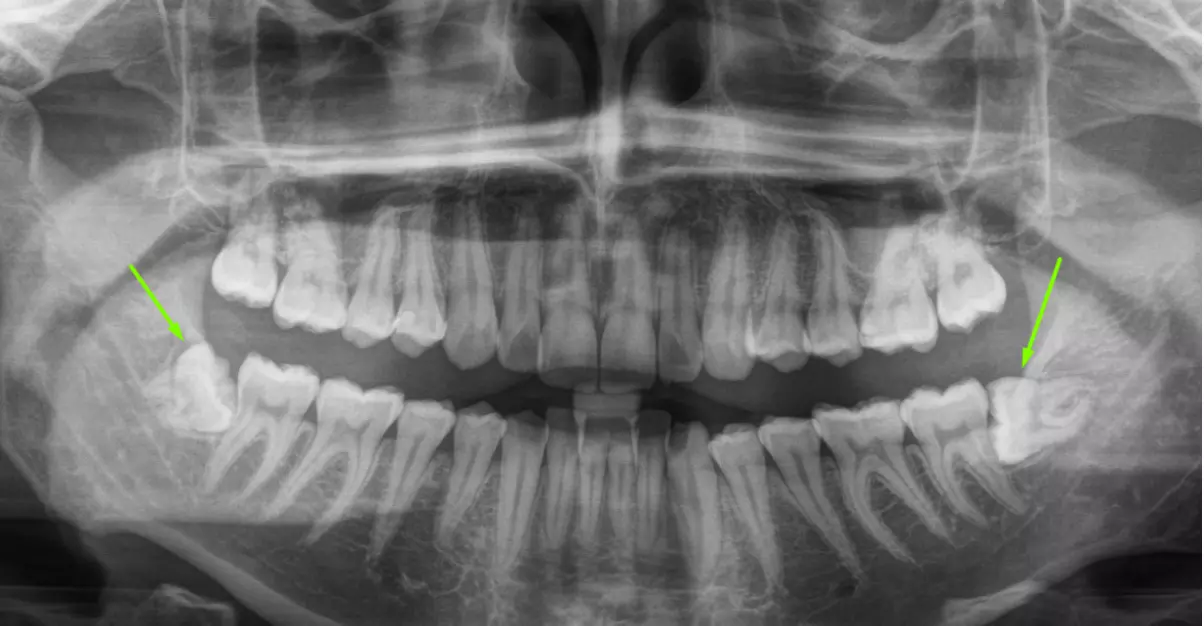

восьмерки на рентгене

Операции предшествует диагностика – доктор осматривает восьмой зуб, слушает жалобы пациента, делает прицельный снимок. Иногда этого недостаточно и стоматолог назначает компьютерную томографию или панорамный снимок. Обычно удаление зубов мудрости – плановая операция. Но если пациент поступает с острыми жалобами и настаивает на удалении, врачи NikaDent Family готовы помочь. Однако, мы всегда информируем пациентов, что это не самый оптимальный вариант. Лучше всего дождаться стихания воспаления и тогда запланировать удаление. Так как в острой его фазе воспаления анестезия наступает хуже, удаление болезненнее, а заживление – дольше. Профессиональная установка керамических виниров в нашей клиники. Вырвать зуб мудрости в Одессе можно двумя способами: обычно или атипичное удаление. Объясняем разницу.